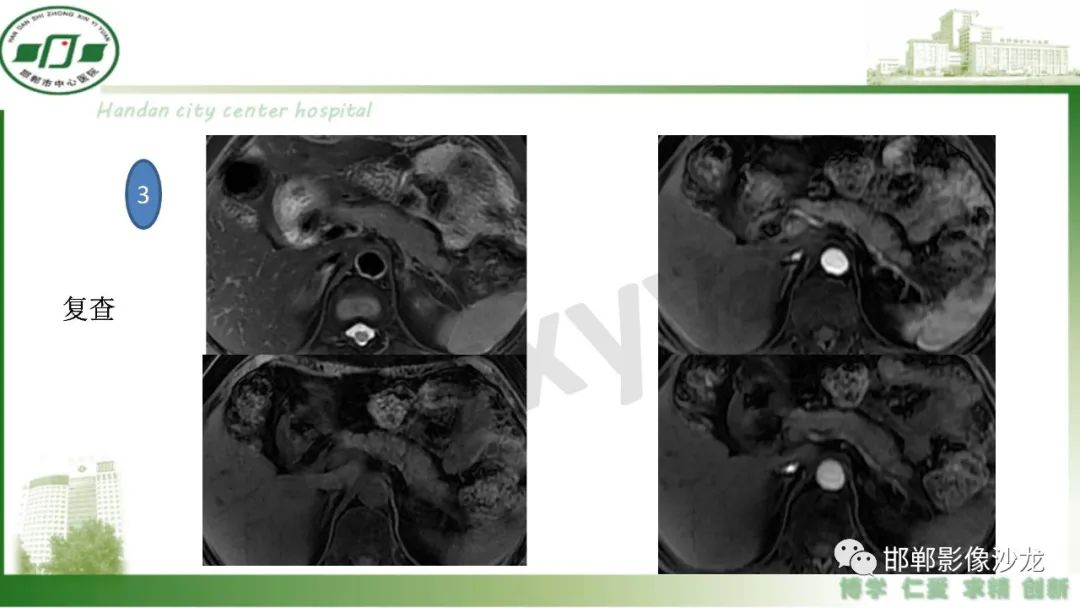

肿块性胰腺炎与胰腺癌的临床、实验室检查、影像学表现有时候很难鉴别,但两者的临床处理、预后又有很大的不同,因此我们平时工作中需要注意两者之间的区别,谨慎诊断,力争为患者及临床带来更大的帮助。